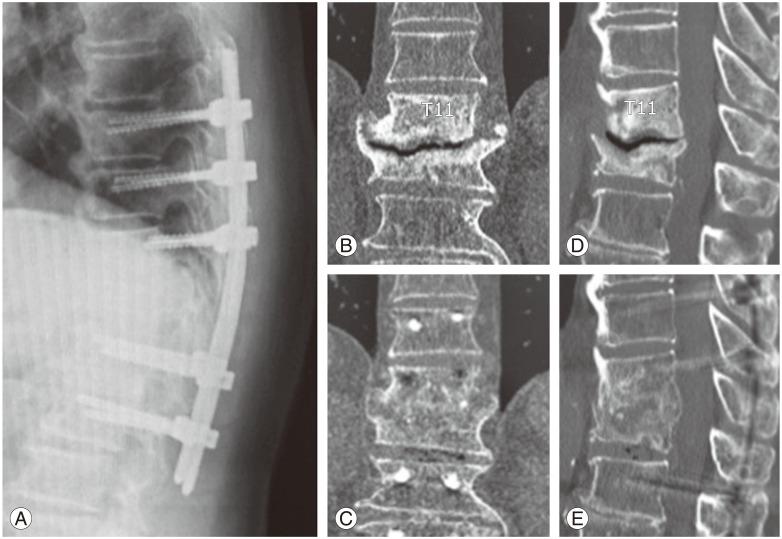

This report introduces a percutaneous transpedicular interbody fusion (PTPIF) technique in posterior stabilization using percutaneous pedicle screws (PPSs). An 81-year-old man presented with pseudoarthrosis following pyogenic spondylitis 15 months before. Although no relapse of infection was found, he complained of obstinate low back pain and mild neurological symptoms. Radiological evaluations showed a pseudoarthrosis following pyogenic spondylitis at T11-12. Posterior stabilization using PPSs from Th9 to L2 and concomitant PTPIF using autologous iliac bone graft at T11-12 were performed. Low back pain and neurological symptoms were immediately improved after surgery. A solid interbody fusion at T11-12 was completed 9 months after surgery. The patient had no restriction of daily activity and could play golf at one year after surgery. PTPIF might be a useful option for perform segmental fusion in posterior stabilization using PPSs.